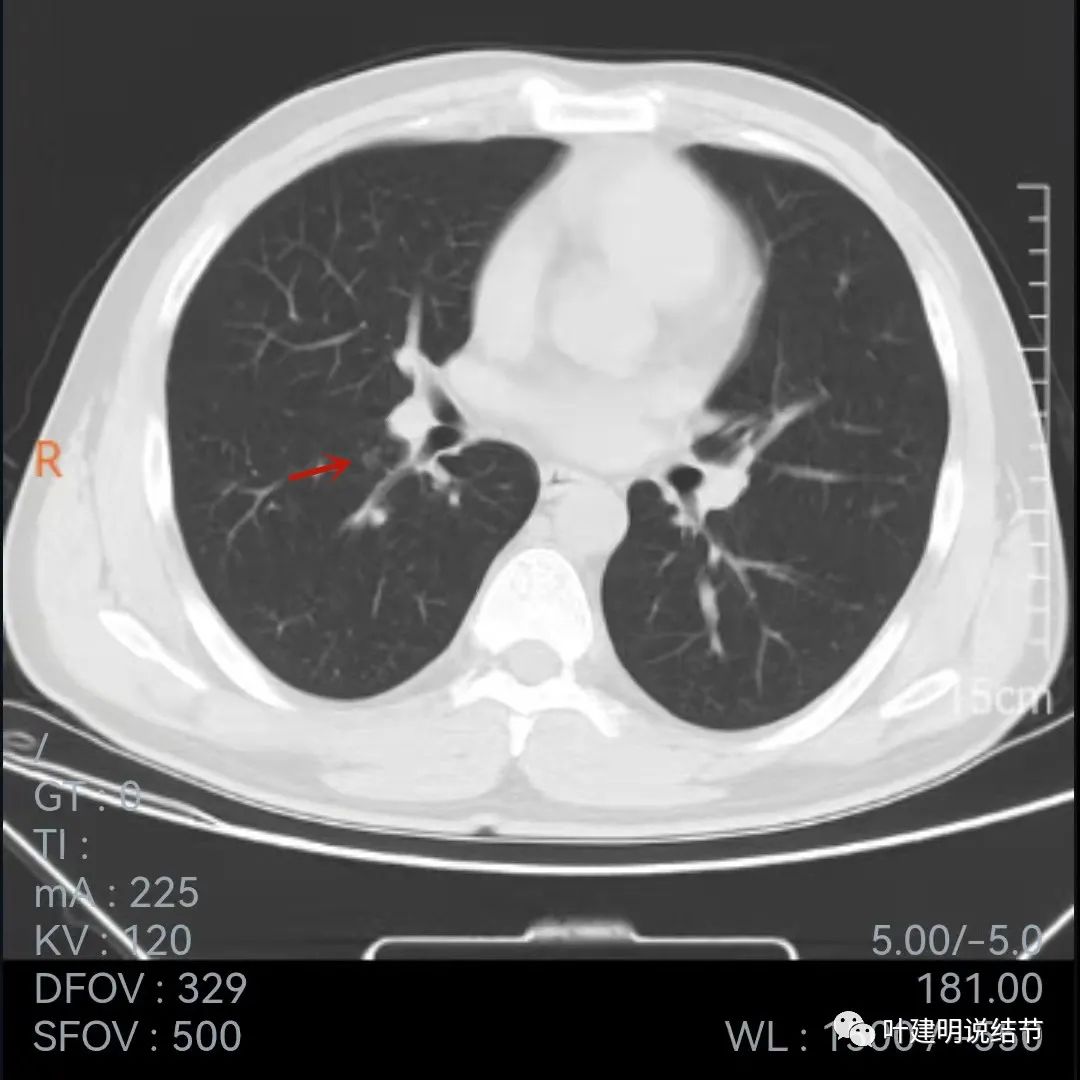

再来看下面薄一点的,也是2020年7月的图像:

叶间胸膜牵拉

牵拉明显

中间密度略低(黄色箭头),前部边缘似有少许毛刺或毛糙的感觉(紫色箭头)

叶间胸膜牵拉凹陷

上图层面密度略不均

与前一年相比,病灶略有不同,感觉边缘粗糙起来,胸膜凹陷较前明显,但因为薄层与非薄层的区别,可比性略差。